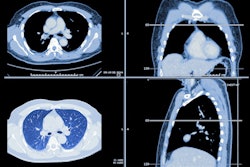

A team led by Dr. Ali Farhat of Albert Einstein College of Medicine in New York reviewed charts from between March 2020 and June 2021 for 2,537 patients; of these, 9%, or 231, were diagnosed with COVID-19 infection via positive SARS-CoV-2 polymerase chain reaction (PCR) or positive antibody test. The team also tracked incidents of hospitalization and any COVID-19-related deaths.

The group found that 9% of patients reporting to Albert Einstein's lung cancer screening program developed COVID-19 during the first 16 months of the pandemic. Of these, almost a third were hospitalized; mortality rate was 6.9%, and was associated with multiple comorbidities, the team noted.